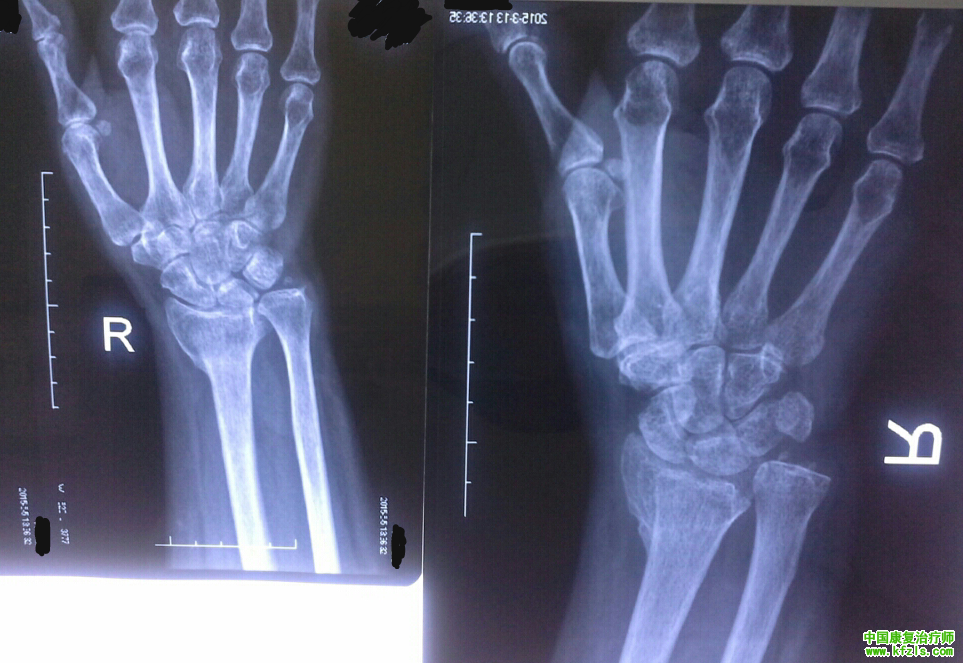

再补充一个病例~虽然不是上面视频里的患者,不过都是一样的骨折,就是陆教授在视频里说前面那个年轻一些的患者。

女性,50多岁,14年12月初骨折的,4月初来我院开始康复的。

主要就是按照陆教授上面的一些手法,然后一天两次,每次半小时,治疗前先蜡疗,治疗后理疗消炎。到现在总共治疗了约40次了吧。

然后先放片子的对比:(左边是5月5日拍的,右边是刚来的时候3月中旬拍的)

效果还是挺明显的吧~{:4_86:}

功能上也恢复的挺好的~一开始患手不敢使劲,现在洗衣做菜这些家务都可以做了~关节活动度也有明显改善~

原本这个病人刚来的时候我给我一个干骨科的同学看过这片子,他说这种情况康复也没用了,一开始给这个病人做治疗的时候也挺没头绪的,结果后来有陆教授指导以后做了一个月就有了很不错的效果~~~